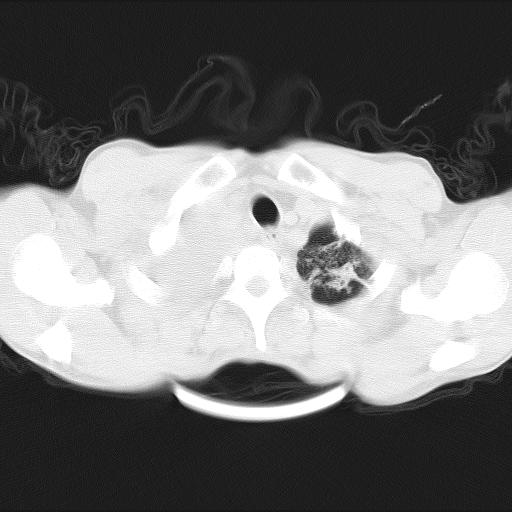

男性,44岁,结核病史多年。现胸闷气短,咳嗽,偶咳血。

1)两肺继发性肺结核伴空洞形成,左肺多发性结核球。2)右侧大量胸腔积液伴右肺部分膨胀不全。3)纵隔淋巴结肿大。

1,双肺多发结节 并空洞影改变, 左侧胸腔积液并部分包裹, 结合原病史首先考虑结核. 但也不除外其它.

2,左侧有一根肋骨陈旧性骨折? 建议追查 .

吉大一院胸水抽检结果:结核性胸水